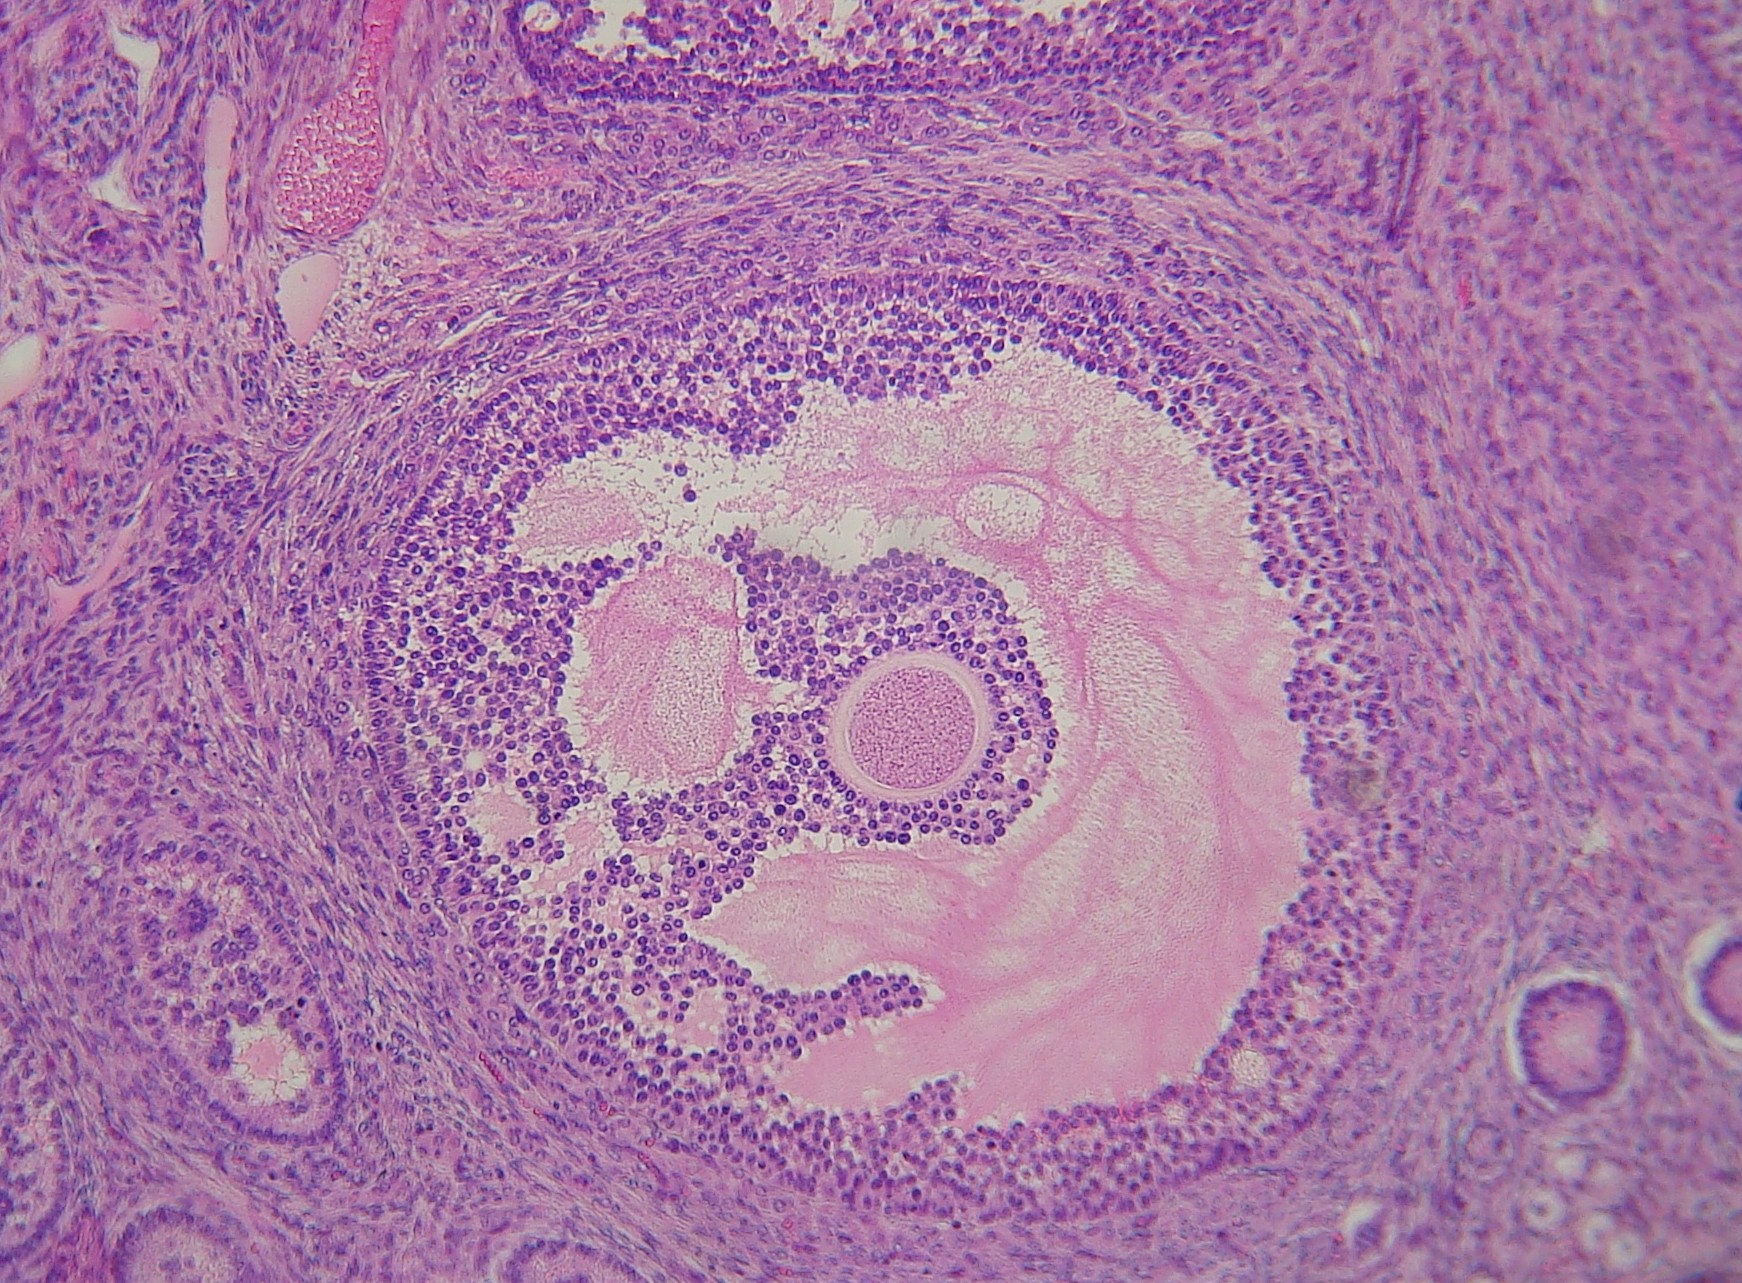

Follicule III cavitaire mûr

Remarquer un follicule mûr au centre du cliché. L'ovocyte I est observable au centre du follicule, en rose clair, l'antrum (= cavité) entouré de la granulosa (bleu violet (cellules granuleuses) et les thèques séparées de la granulosa par un petit décollement de la préparation.